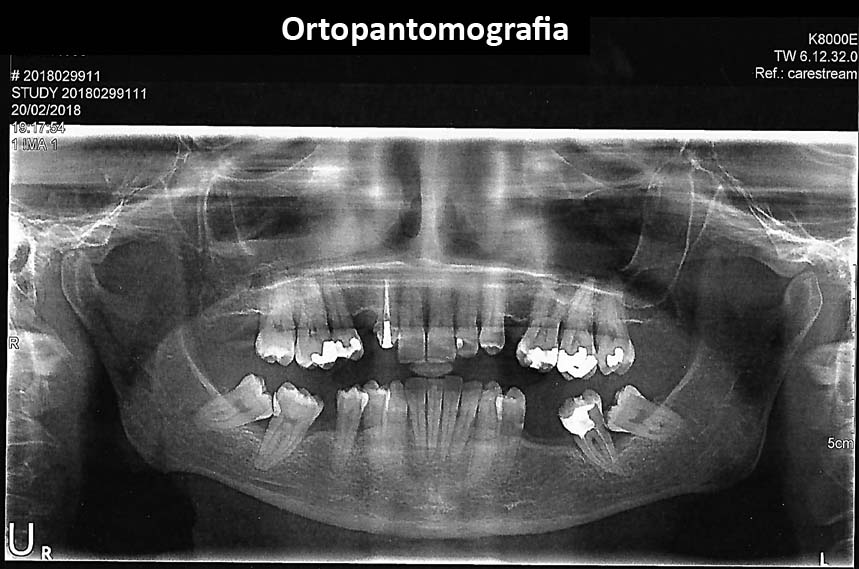

All information necessary to diagnose are taken:

• Clinical examination

• Radiographies/X´Rays

After all information is taken a diagnosis is done and a treatment plan is discussed and decided in the patient´s best interest.